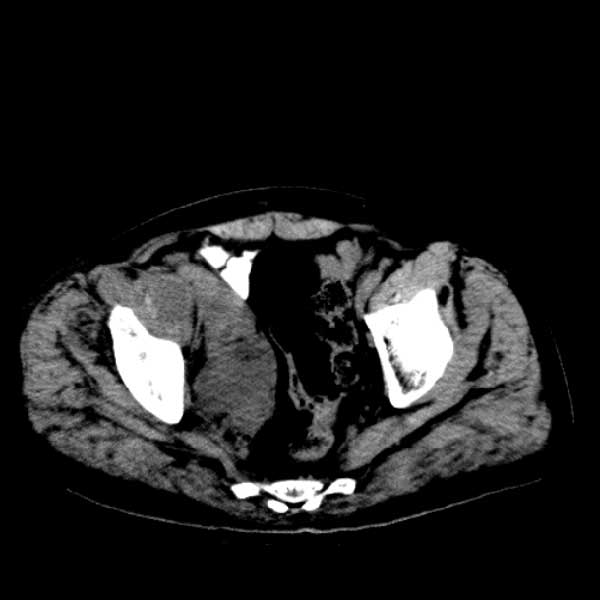

标题: CT13513:男 71 腹部疼痛20余天,近几天高热就诊,骨窗未见异 [打印本页]

标题: CT13513:男 71 腹部疼痛20余天,近几天高热就诊,骨窗未见异

考虑感染性病变可能性大,起源于阑尾?

感染,脓肿形成

考虑为化脓性阑尾炎.脓肿形成.及多肌肉累及.

考虑右侧腰大肌脓肿,向右髂窝、右腹股沟流注。

支持化脓性阑尾炎伴右髂窝脓肿、腰大肌腰方肌脓肿形成。

考虑腹腔及盆腔化脓性炎症,累及右侧髋关节及腹股沟区.

首先考虑化脓性阑尾炎伴腰大肌、腰方肌脓肿,不除外回盲部结核。

回盲部癌待排除。

患者肠镜检查考虑结肠癌,病理证实

患者肠镜检查考虑结肠癌,病理证实。肺部ct可见多发结节,考虑转移